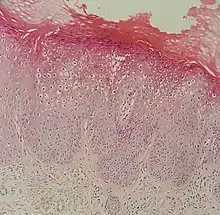

Micrograph of a flat wart

Flat warts, technically known as Verruca plana, are reddish-brown or flesh-colored, slightly raised, flat-surfaced, well-demarcated papule of 2 to 5 mm in diameter. Upon close inspection, these lesions have a surface that is "finely verrucous".[1][2] Most often, these lesions affect the hands, legs, or face, and a linear arrangement is not uncommon.[2] At histopathology, flat warts have cells with prominent perinuclear vacuolization around pyknotic, basophilic, centrally located nuclei that may be located in the granular layer.[3] These are referred to as "owl's eye cells."[3]